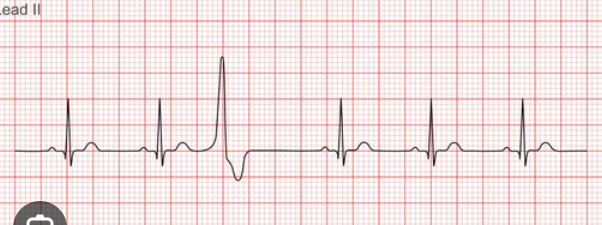

term image

sinus brady cardia

CAUSE: hypoxia, hypothermia, well trained athlete

Symptoms: chest pain, hypotension, SOB, sweat

TX (only if symptoms); atropine